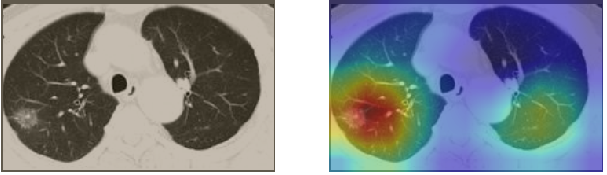

A wide variety of typical and atypical CT abnormalities have been reported for COVID-19 patients in various studies [58, 59]. So, we tested our models on external CT images extracted from these two publications as they feature typical findings of COVID-19 pneumonia marked by specialists. In order to make sure that not any of the extracted images are unintentionally included in our datasets, specifically the COVID19-CT dataset, we use the model trained on the SARS-CoV-2 dataset. First, the InceptionV3 model is employed to classify the extracted CT images. The model is able to correctly classify the given CT images as COVID-19. Second, in order to interpret the model’s generalization capabilities, we apply the Grad-CAM technique to visualize the regions of abnormalities that are considered. By assessing the different CT images in Figure 15, we can see that the model accurately localizes the disease-related regions. Even more interesting is the fact that the model ignores any specific marks in the images like letters and only localizes the COVID-19 related regions. These visual explanations show the success of our models to learn relevant, generic visual features related to COVID-19 and are capable to correctly classify CT images outside the datasets on which they are trained.

Figure 16 shows various CT scans where only one lung is visible. The CT scans are also extracted from the paper [58] and show different CT manifestations of COVID-19 pneumonia marked by red squares. The InceptionV3 model is capable to classify them correctly as COVID-19, although it is trained on CT scans where the entire lung is visible. Intriguingly, when applying Grad-CAM we can see that all regions of abnormalities are accurately localized. This also proves the potential of our model to detect COVID-19 abnormalities in CT images outside the dataset used for training.